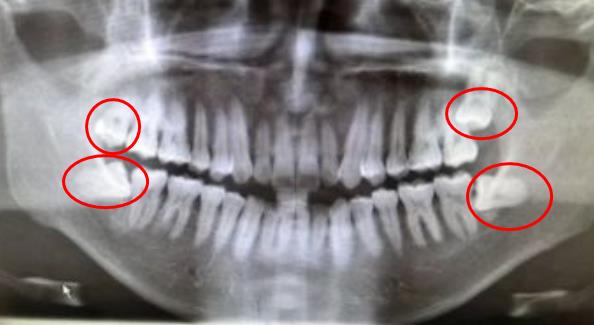

通常來說,幾天到一周左右,智齒炎症會(hui) 慢慢消除,疼痛腫脹也逐漸好轉。但並不是這樣就能完事了。這時候是著手處理立事牙的好時機,建議及時到醫院拍片查看智齒的情況,然後確定是否需要進行拔除。

拔除的智齒

如果是位置不正、傾(qing) 斜頂著前麵鄰牙、自身齲壞等大部分的智齒,可能都是需要麵臨(lin) 拔除的,隻有很小的一部分有對合牙、位置正能發揮咀嚼功能或者完全埋伏於(yu) 牙槽骨,不會(hui) 有什麽(me) 影響的才建議保留。當然,如果有特殊情況,比如說有大牙缺失想要正畸的,可以先找正畸醫生評估一下,智齒是否可以廢物利用不用拔除。